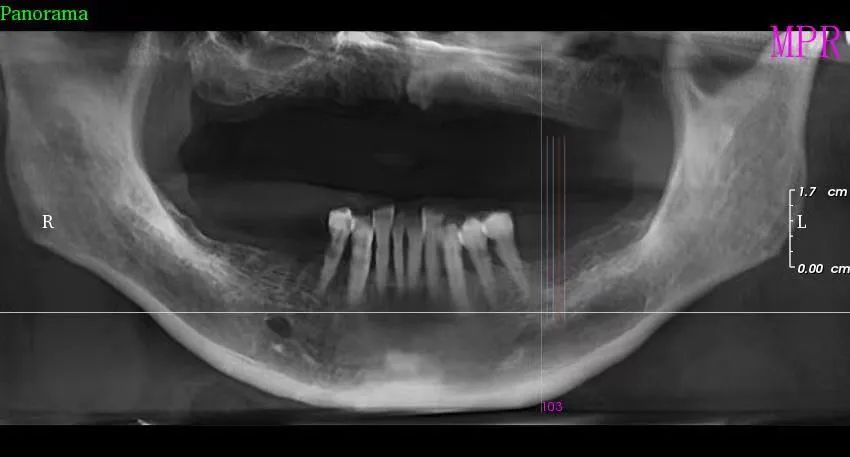

三、種植牙技術

目(mù)前,社會上很多(duō)人被牙齒缺失所(suǒ)困擾,牙齒缺失不但影響人的咀嚼和(hé)語言功能,對於人的(de)麵(miàn)部(bù)美觀也是一種影響,甚至有些人因(yīn)缺失牙齒而(ér)不願意張口說話,種植牙被譽為(wéi)人類“第(dì)三(sān)副牙齒”,因其舒適(shì)、美觀(guān)、功能(néng)好而被缺牙患者追捧。經衛生(shēng)健康委批準,我院於2023年(nián)3月18日正式(shì)開展種植(zhí)牙技術,開(kāi)展當天門診手術7例共計14顆植體,術(shù)後1天回訪患者表示無紅腫、無疼痛症狀(zhuàng),術後(hòu)7天回訪(fǎng)一切良好無異常,術後10天拆線創口愈合良好,自開展口(kǒu)腔種植手術以來,有許多患者紛紛到科裏(lǐ)進行相關谘詢和(hé)檢查,更是不斷有患(huàn)者預約意向種植,我院嚴格按照江(jiāng)西省醫療保障局、江西省衛生健康委員(yuán)會(huì)關於(yú)公布實施口腔種植類醫療服務價格有關事項的通知—贛醫保字《2023》3號文(wén)件執行操作,在手術診療中,嚴(yán)格操作流程,減少感染風險。我院(yuàn)口腔種植技術的成功和發展,不僅完善了傳(chuán)統牙齒修複(fù)技術的不(bú)足,而且在功能與(yǔ)美觀上給了(le)人們嶄新的體驗,我院致力於提供一站式口腔種植診療服務,必將為(wéi)本縣及周邊缺(quē)失牙患者找回美麗、自信的微笑。

手(shǒu)術中(zhōng)

案例(lì)一

種植前與種植後

案例二

種植前與種植(zhí)後